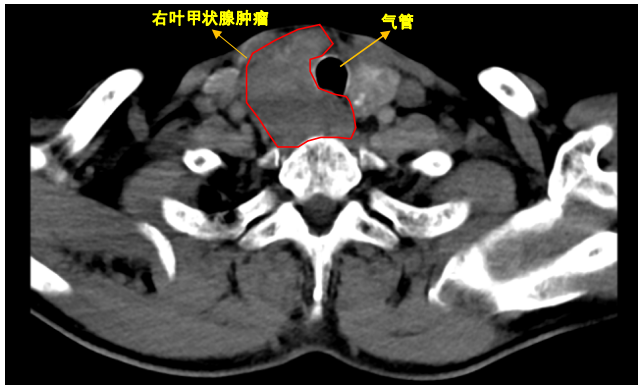

CT检查结果,令他直接吓瘫—— 甲状腺肿物把气管压变形 ,双肺还长出可疑结节!再经过B超和穿刺活检,确诊为甲状腺双叶乳头状癌+淋巴结转移 !

图片